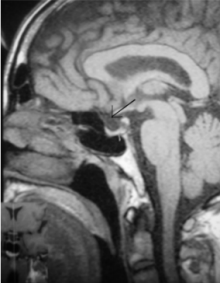

图 3 蝶鞍 MRI:垂体窝呈液型信号,垂体上缘受压凹陷,垂体变薄,信号均匀,垂体柄居中无增粗,视交叉显示无异常,鞍旁未见异常占位性病变。显示为空泡蝶鞍。

患者, 男, 63 岁,工人,以“双眼视力突然下降 8 d”之主诉于 2007 年 8 月 21 日入院。8 d 前无明显诱因出现双眼视力突然下降,伴左眼前固定黑影,无眼球运动痛,无眼胀,无头痛。在当地某三级甲等医院诊断为 “双眼视乳头水肿? 双眼视乳头炎? ”,给予甲钴铵、复合维生素 B、复明片等药物口服,疗效欠佳。后来我院就诊,门诊检查后以“双眼视乳头水肿”之诊断收住我院。患者有12年高血压病史,口服药物治疗,血压控制良好。入院查体: T 35.6℃,P 62 次 /分 , R 19 次 /分 , BP 140/90(1 mmHg=0.133 kPa) , 心、肺、腹无明显异常。右眼视力(矫正视力, 以下同) 0.5 ,左眼视力 0.25。眼压(Non-contact tonometer, NCT) : 右 10.7 mmHg, 左 10.9 mmHg。双外眼正常,双眼眼球运动及眼位正常。双眼角膜透明, 直径约 11 mm。前房深度正常,房水闪辉阴性,细胞阴性。双眼瞳孔直径 3 mm,居中,圆,直接光反应和间接光反应灵敏。双眼晶体位置正常、密度增高,双眼玻璃体透明。双眼视盘边界不清,呈绒毛状,色淡红,C/D= 0.3,动脉细,静脉极度充盈, A/V= 1:2, 视盘周围有片状出血,视盘周边网膜水肿,黄斑中心凹反光不清(图1A、图1B) ,左眼眼底情况较右眼严重。视野检查:双眼视野缩小,生理盲点扩大。入院诊断为: 双视乳头水肿原因待查。完善常规检查,血尿粪常规、心电图、胸部 X 线正位片、肝肾功均无异常。血糖、血脂和血流变检查无异常。患者曾在当地某三级甲等医院拍摄颅脑CT(图2),结果无明显异常。入院后当天行颅脑 MRI 检查,未能清楚显示蝶鞍。2007 年 8 月 22 日进行视觉电生理检查: 双眼 ERG-b 波幅稍低,双眼P-VEP峰时稍延长、振幅低,提示双眼视网膜及视传导功能减退。予以葡萄糖、ATP、辅酶 A、胞二磷胆碱、甲钴铵静脉滴注 。2007 年 8 月 24 日复查双眼视力, 右眼视力升至 0.8, 左眼视力升至 0.4。2007 年 8 月 27 日行腰椎穿刺术, 脑脊液测压力为 170 mmH2O, 颅内压正常。脑脊液常规检查结果正常,脑脊液葡萄糖 4.8 mmol/L、氯 117.6 mmol/L、免疫球蛋白 18.1 mg/dL。双下肢神经诱发电位结果大致正常,双侧脑干听觉诱发电位结果可疑,提示Ⅰ~Ⅴ波波间期稍延长。行蝶鞍 MRI(Magnetic resonance imaging, MRI),影像学表现为: 垂体窝呈液型信号,垂体上缘受压凹陷,垂体变薄,信号均匀,垂体柄居中无增粗,视交叉显示无异常,鞍旁未见异常占位性病变,确诊为空泡蝶鞍(图3) 。患者无鞍内或鞍旁区手术放疗病史,考虑为原发性空泡蝶鞍综合征引起的双眼视乳头水肿。2007 年 8 月 31 日转入神经外科,继续予以能量和营养神经药物治疗。于 2007 年 9 月 6 日行全麻下开颅鞍区探查术,术前右眼视力已恢复为 1.0,左眼视力为 0.4。术中见双侧视神经处蛛网膜粘连并疝入鞍内,左侧视神经下陷明显。术中充分松解双侧视神经周围蛛网膜,左侧视神经下垫衬明胶海绵使之抬起。术后患者自觉左眼视物较前清晰,2007 年 9 月 13 日查右眼视力为 1.0,左眼视力为 0.5,眼底表现较前好转。2008 年 5 月 27 日复查时右眼视力为 1.0,左眼视力恢复至 0.8,双眼底表现基本正常(图4A、图4B) ,未能进行蝶鞍MRI检查。